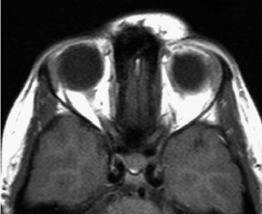

PHACE syndrome

- je asociácia medzi IH a malformáciou očí, srdca, veľkých artérií a mozgu.

- bol prvýkrát popísaný Dr. Ilona Freidan v roku 1996.

- Posterior fossa brain malformations

- Haemangiomas, particularly large, segmental facial lesions

- Arterial anomalies

- Cardiac anomalies and coarctation of the aorta

- Eye abnormalities and endocrine abnormalities